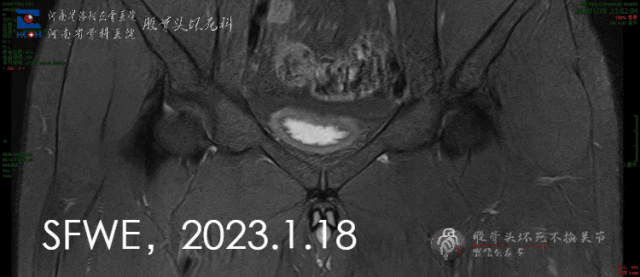

磁共振检查如下,很常见、很普通的一种坏死。